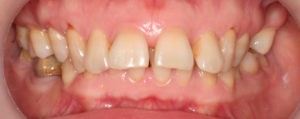

Пациентка, 43 года обратилась в клинику с жалобами на наличие промежутков между зубами, измененный наклон передних зубов верхней челюсти, появившейся за последнее время. Также пациентку беспокоил изменившийся профиль лица.

Для предварительной подготовки были привлечены пародонтолог и ортопед, поскольку отсутствие нескольких зубов, заболевание пародонта и дефекты твердых тканей зубов сопутствовали основной патологии. Проведены пародонтологические процедуры, вылечен кариес и его осложнения, изготовлены временные коронки для зубов с большим разрушением. На фото — временные коронки на боковых зубах.

Искривление окклюзионной кривой (плоскости смыкания зубов), возникшее в результате парадонтита, успешно удалось устранить, используя накусочные брекеты на верхних резцах и микроимплант, установленный во фронтальном участке нижней челюсти: